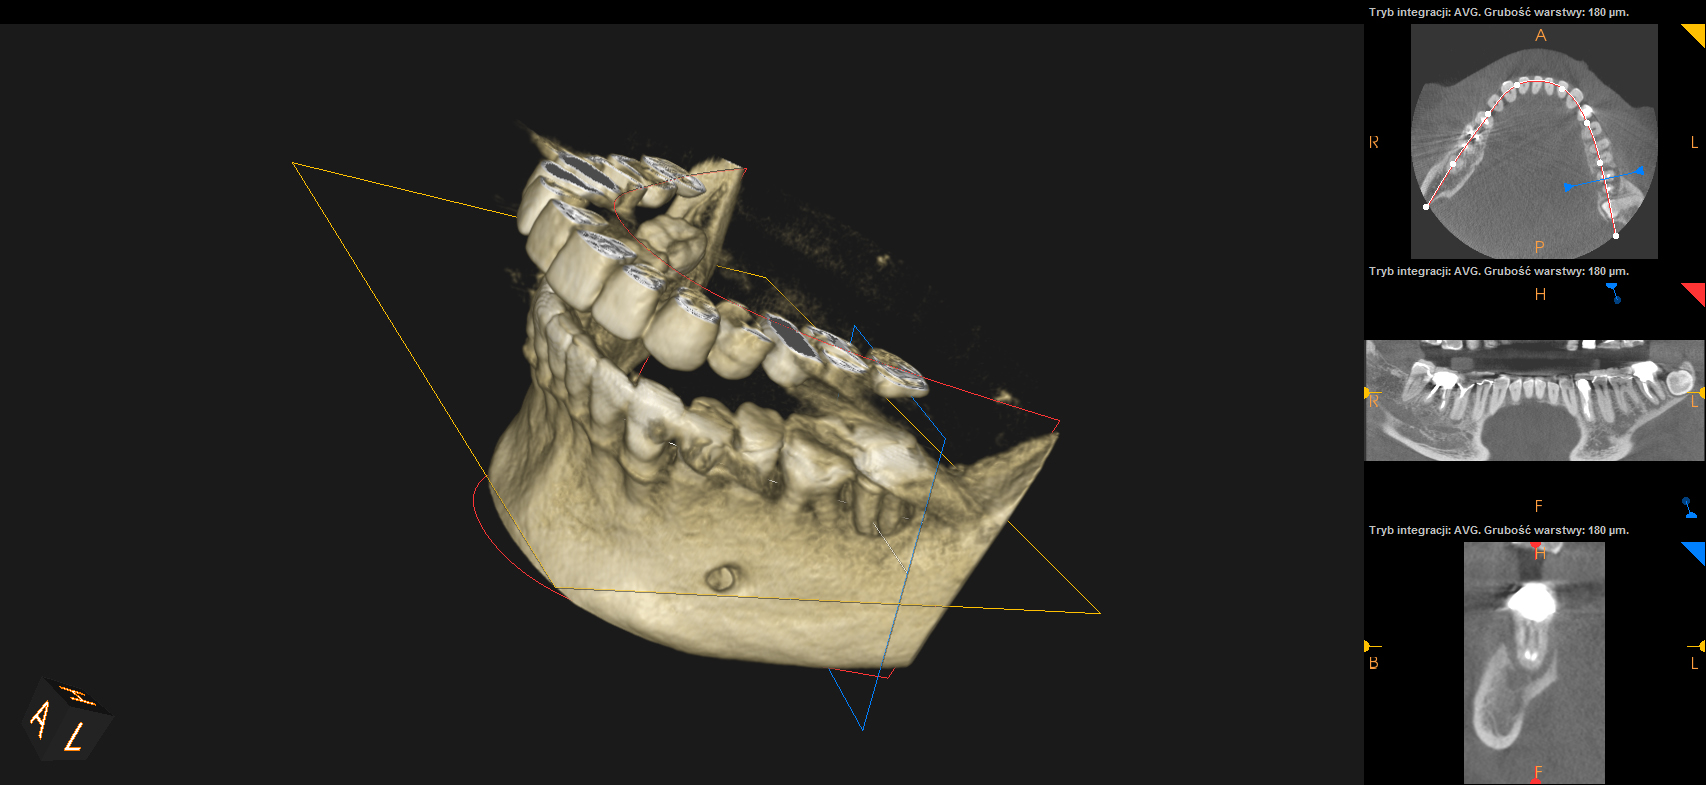

Ten problem najczęściej dotyczy zębów trzonowych żuchwy oraz górnych przedtrzonowców. Może również towarzyszyć wadom zgryzu, w zębach zniszczonych przez erozję, abrazję lub atrycję. Pionowe złamanie korzenia jest trudne do zdiagnozowania. Zdjęcia RTG nie zawsze bowiem ukaże „całą prawdę”. Coraz powszechniej używane obrazowanie CBCT (3D) pomaga w postawieniu diagnozy pionowego złamania zęba lub korzenia.

Do pionowego złamania korzenia zęba może dojść podczas zabiegu leczenia kanałowego poprzez używanie zbyt dużej siły w czasie wypełniania lub oczyszczania kanału. Może być również spowodowane zaklinowaniem się narzędzia w kanale. Pionowe korzenia zęba zawsze prowadzi do usunięcia całego zęba. Dbałość o profilaktykę i terminowe zgłaszania się do gabinetu stomatologicznego z towarzyszącą diagnostyką rentgenowską znaczącą redukuje te ryzyka.